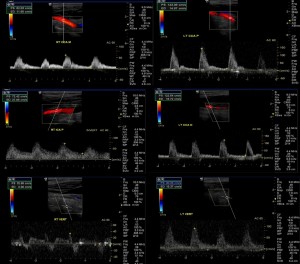

The problem – Carotid artery stenosis is diagnosed mainly according to elevation of the peak systolic velocity. However, if there are two lesions in tandem, the upstream lesion may dampen the velocity that is observed between the lesions. If the velocity is not dampened that strengthens the chance that the second finding is real. Also, examining the waveform is even more important than usual in this case.

When should this be suspected – if there is a discrepancy between the B-mode images and the peak systolic velocity.

The solution – The second lesion should be sought. In order to produce peak systolic velocity dampening it is often at least 3 cm further upstream. It may be still detectable by ultrasound or it may be intracranial. In that case transcranial Doppler or vascular brain imaging (MRA or CTA) need to be performed.

Common carotid artery origin and aortic valve stenosis

The problem – Proximal stenosis of the common carotid artery are common and can be a source for atheroembolic stroke. They are, however, not directly visualized by duplex ultrasound.

When should this be suspected – Reduced peak systolic velocity throughout the common carotid artery and internal carotid artery and ‘parvus et tardus’ waveform pattern.

The solution – If the problem is a common carotid or subclavian artery stenosis, then the dampened velocities will be seen on one side only and comparison to the other side should suggest the diagnosis.